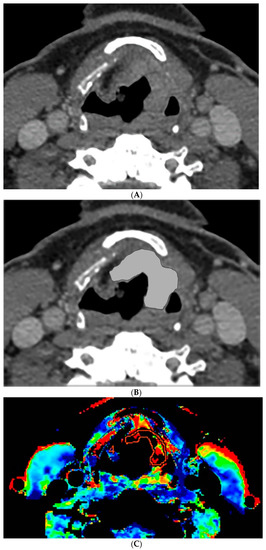

The perfusion data post processing was performed on a commercially available Perfusion-4 software package on an Advantage Windows Workstation version 4.0 (General Electric Medical Systems, Milwaukee, WI, USA). An oval region of interest was placed in the internal carotid artery to generate the contrast arterial enhancement curve. Radiologist 1 (a fellowship trained neuroradiologist with 15 years of experience in head and neck imaging) drew additional freehand regions of interest contouring the tumor along its margin on all axial images where the tumor was visible, and an oval region of interest in normal muscle tissue. An example of the region of interest through the tumor is demonstrated in Figure 1 and Figure 2. The perfusion data were post processed by a deconvolution-based method into maps that represented permeability surface area product (PS), blood flow (BF), blood volume (BV), mean transit time (MTT), and time-to-maximum (Tmax).

Figure 1.

Computer tomography (CT) and perfusion sections of laryngeal carcinoma on pre-treatment images. Axial sections show the grayscale image (A) and outlines for the following: computer (B) and perfusion image (C). Note that the region of interest (ROI) drawn on the CT perfusion image appears different in size from that on the contrast enhanced image; this is because the CT perfusion images are 5 mm in slice thickness whereas the conventional CT images are 1.25 mm in slice thickness (implying that the CT perfusion data is a composite of 4 adjacent 1.25 mm slices from conventional CT).

The percent volume change ICC of the computer with Radiologist 1 or Radiologist 2 were 0.80 and 0.74, respectively. The percent volume change ICC between the two radiologists was 0.73. The differences in the computer-versus-radiologist and radiologist-versus-radiologist ICCs did not achieve statistical significance. Examples of the semi-autonomous computerized 3D level-set segmentation are demonstrated in Figure 1 and Figure 2.